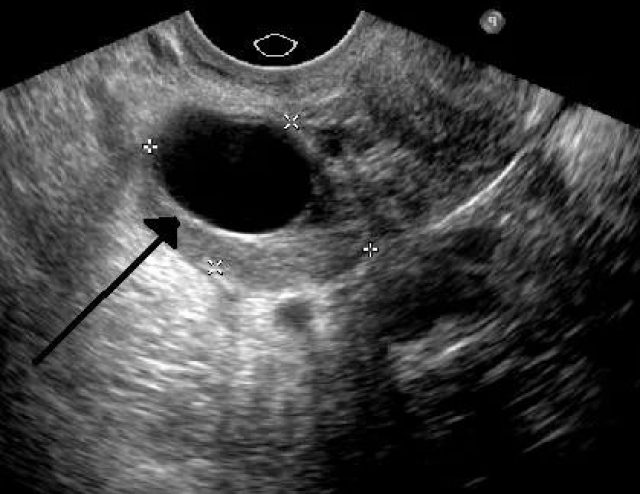

Затем обязательно назначается ультразвуковая диагностика органов малого таза. Также это исследование помогает выявить патологии внутриутробного развития плода, если женщина беременна.

На УЗИ выявляется большие затемнения, которые могут указывать на развитие тератомы

- УЗИ с применением цветного допплеровского картирования (ЦДК). Зрелые тридермомы выявляются как округлые образования с разнообразной внутренней структурой. Содержимое более плотное по сравнению с окружающими тканями. Кроме того, заметны мелкие плотные включения внутри тератомы: хрящи, кости, волосы. Кровоток в зрелых опухолях не определяется. При тератобластоме ЦДК обнаруживает картину в виде мозаики с большим количеством сосудов. УЗИ рядом расположенных органов позволяет установить, имеются ли метастазы (при озлокачествлении).